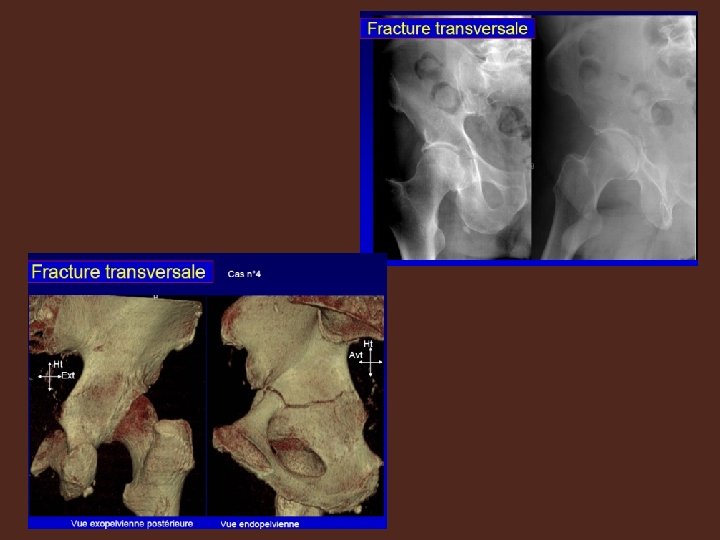

RADIOLOGIE : • fait le diagnostic. • A la base de la classification de JUDET LETOURNEL Le bilan comprend systématiquement I. LA RADIOGRAPHIE: • Bassin de face • Hanche malade de face • 3/4 alaire, 3/4 obturateur===clichés obliques à 45°

II. LE SCANNER: Indispensable si • Polytraumatisé , inconscient • Fracture visible sur radiographie • Forte suspicion clinique+radiographie négative